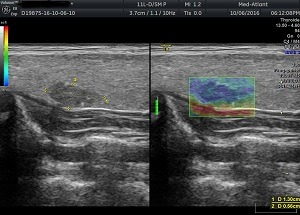

Обстеження проводиться за допомогою ультразвукового обладнання і спеціальних датчиків. На монітор лікарю виводиться еластограма, де різними кольорами позначається щільність тканин. Згідно шкали жорсткості кольорів та коефіцієнту strain ratio – що індивідуально розраховує контрольне значення деформації тканин, лікар робить опис і висновок.

За шкалою кольорів:

1.Синьо-зелений – тканини мають середню жорсткість, за подальшими змінами необхідно спостерігати або застосовувати додаткові методи діагностики (біопсія за показами).

2. Зелено-жовто-червоний колір – тканина низької жорсткості, що є показником доброякісного утворення.

3. Синій колір – є показником тканини високої жорсткості, що вказує на злоякісний характер утворення.